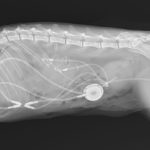

猫さんが急に具合が悪くなって、かかりつけ医を受診したところ血液検査で腎数値が著しく上昇し、高カリウム血症になっているとのこと。すぐに原因を調べて必要な処置をして欲しいとのことで来院されました。無麻酔CTでは尿管結石は確認されませんでした。すぐに拡張した腎盂に腎瘻カテーテルを設置し、尿の排泄路を確保しました。数日後アシドーシス、高カリウム血症は改善されました。尿管炎に伴う尿管の運動機能障害、エックス線に映らない結石の閉塞(99%近くシュウ酸Caなのでまず考えにくい)などが考えられましたが、腎瘻カテーテルを一時的に閉鎖すると腎数値が上昇傾向にあるため、両側の尿管の機能障害と判断しSUBシステム(人工尿管)によるサルベージを行いました。手術の翌日には腎数値は正常に回復しました。CTによる猫の尿管結石の検出感度は非常に高く、術式の決定や治療方針について細かい評価が可能です。今後は血液検査で腎数値のモニタリングを行いながら、定期的にインプラントの洗浄やメンテナンスが必要になります。